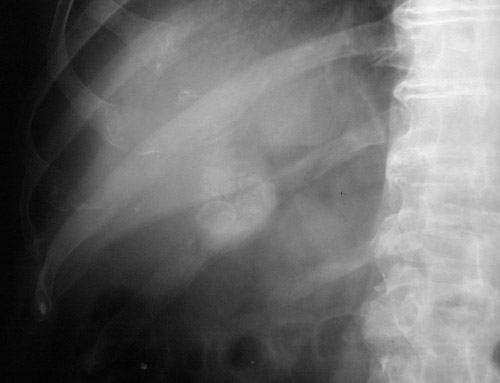

This abdominal radiograph (plain film) demonstrates multiple gallstones seen here within the gallbladder. The presence of a component of calcium bilirubinate in the stones makes them radiopaque and, therefore, visible.